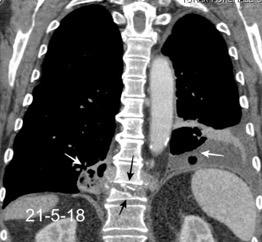

Marzo 2014: Perforación longitudinal distal secundaria a episodio de vómito (síndrome de Boerhaave). Derrame pleural izdo. que evoluciona a empiema.

Wang C-T et al. Tension hydropneumothorax in a Boerhaave syndrome patient: A case report . World J Emerg Med, 2021. Katabathina V et al. Nonvascular, nontraumatic mediastinal emergencies in adults:a comprehensive review of imaging findings. Radiographics. 2011.